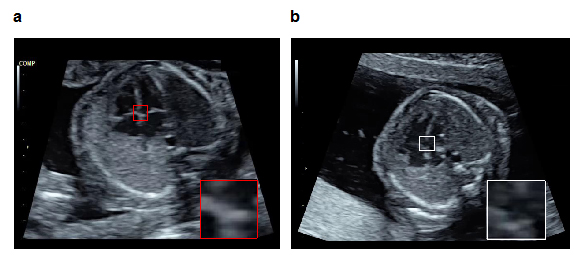

図1 物体検知技術を活用した胎児心室中隔の異常検知例

正常胎児心臓(a)において映っているべき心室中隔を提示し(赤枠),アノテーション済み教師データを用いて学習した物体検知技術を用いて,症例bにおいて実際に映っていた心室中隔の部位を検知する(白枠)。その相違から症例bは異常所見を有すると判定する(b. 心室中隔欠損)。